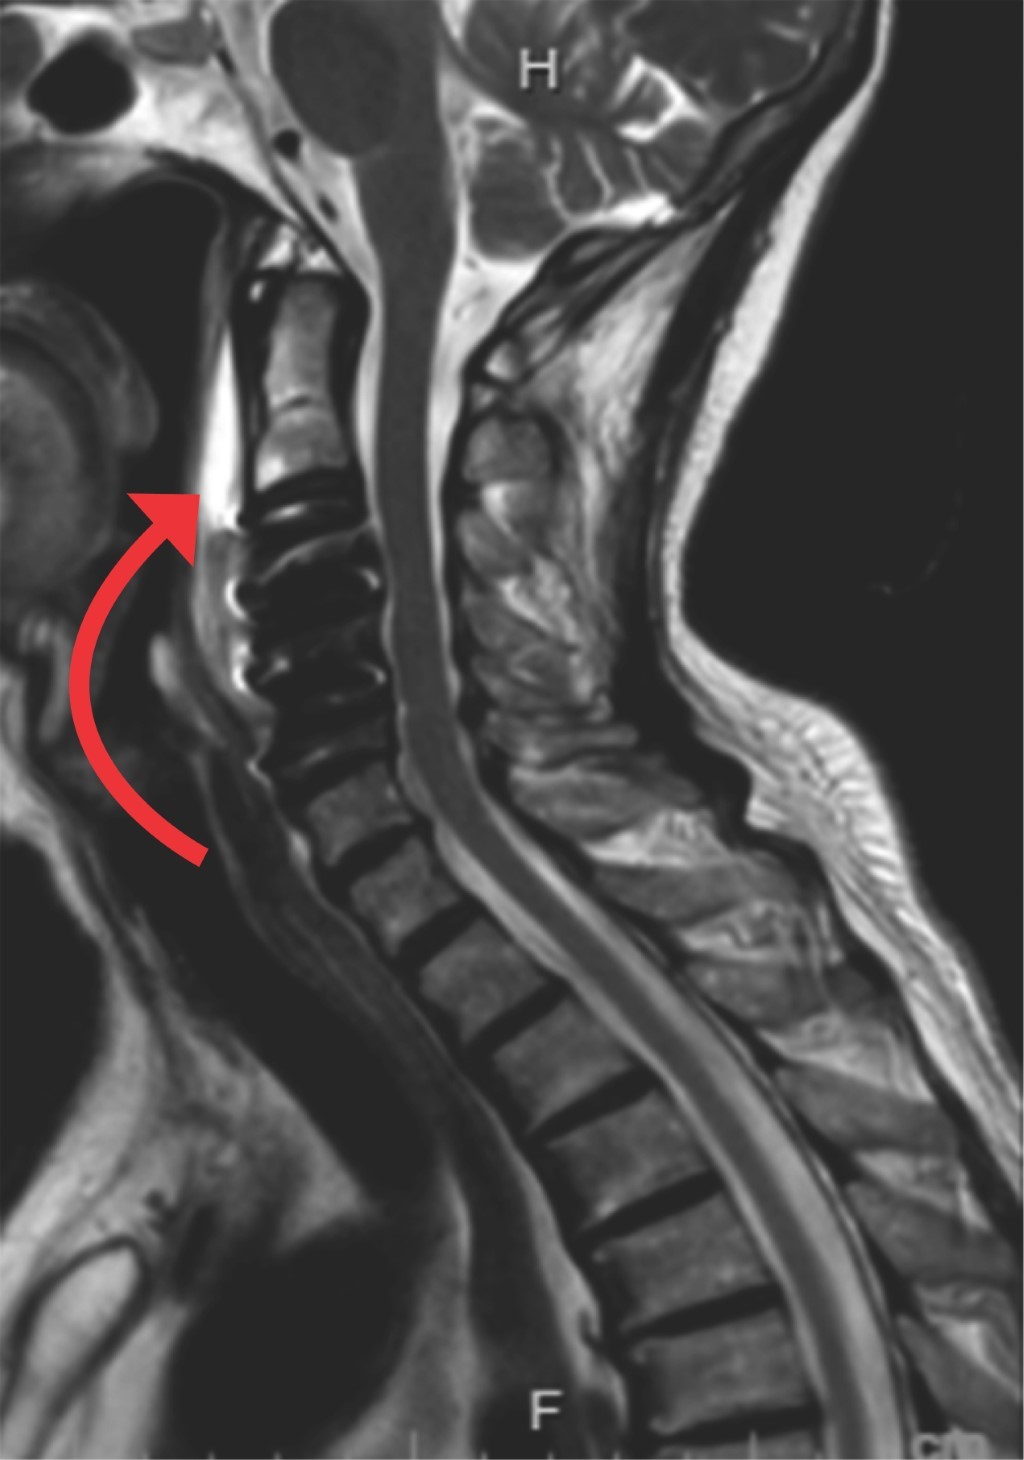

Dentro de las complicaciones derivadas de la discectomía se encuentra la fístula2 de líquido cefalorraquídeo, que si bien no es la más común,1-6 suele presentarse, y si es inadvertida puede derivar en complicaciones catastróficas o incluso fatales tal como la infección de tejidos blandos (Figura 1) y mediastinitis (Figura 2); todo esto debido a que, por la profundidad a la que se encuentra la columna respecto a la herida quirúrgica, es muy probable que no haya fuga de líquido tras la piel tal como sucede en las fístulas que se presentan en columna torácica, lumbar o cervical posterior. Esta condición anatómica originaría que pase totalmente inadvertida y el líquido cefalorraquídeo pueda permear sin obstáculos hacia las estructuras anatómicas anteroinferiores, y en este caso sería el mediastino anterior el receptor de este líquido.

A tres pacientes se les realizó resonancia magnética de columna cervical simple (Figuras 3, 4 y 5), los días de realización variaron debido a que dos de ellos se encontraban en institución pública y la accesibilidad a la resonancia magnética no pudo ser inmediata. En los tres se presentó una hiperintensidad con forma de flecha, la cual se localizaba en el espacio prevertebral y que llegaba hasta C1-C2 (Figuras 3, 4 y 5). La hiperintensidad era isointensa respecto al líquido cefalorraquídeo que se observaba en el conducto raquídeo. En uno de los casos se pudo documentar un trayecto fistuloso, pero no fue constante en ninguno.

Como se puede observar en las imágenes previas, en la secuencia T2 en un corte sagital puede observarse una hiperintensidad en el espacio intervertebral que nos indica que en ese sitio se encuentra impregnado de líquido cefalorraquídeo, ya que la hiperintensidad es igual a la observada en el conducto raquídeo.

Como se puede observar en las imágenes previas, en la secuencia T2 en un corte sagital puede observarse una hiperintensidad en el espacio prevertebral que nos indica que en ese sitio se encuentra impregnado de líquido cefalorraquídeo, ya que la hiperintensidad es igual a la observada en el conducto raquídeo.

En el primer caso se observa que el líquido se encontraba hacia arriba y hacia abajo del sitio operado y el grosor de la hiperintensidad prevertebral era sumamente grande y que había discreta migración hacia el mediastino, lo que orilló a tomar la decisión de reintervenir a la paciente inmediatamente para cierre de fístula. Esto podría considerarse un signo de fístula de alto gasto, sin embargo, no se cuenta con suficiente evidencia como para sustentarlo, haría falta más evidencia para poderlo determinar.

El signo de la flecha puede ser un indicador muy fiable para el diagnóstico y seguimiento de las fístulas de LCR originadas en la discectomía de la columna cervical realizada vía anterior (Figuras 6 y 7). La misma se visualiza mejor en la secuencia T2 en el corte sagital de una resonancia magnética simple de columna cervical. Su identificación puede ayudarnos a tomar decisiones sobre esta pequeña gran complicación.